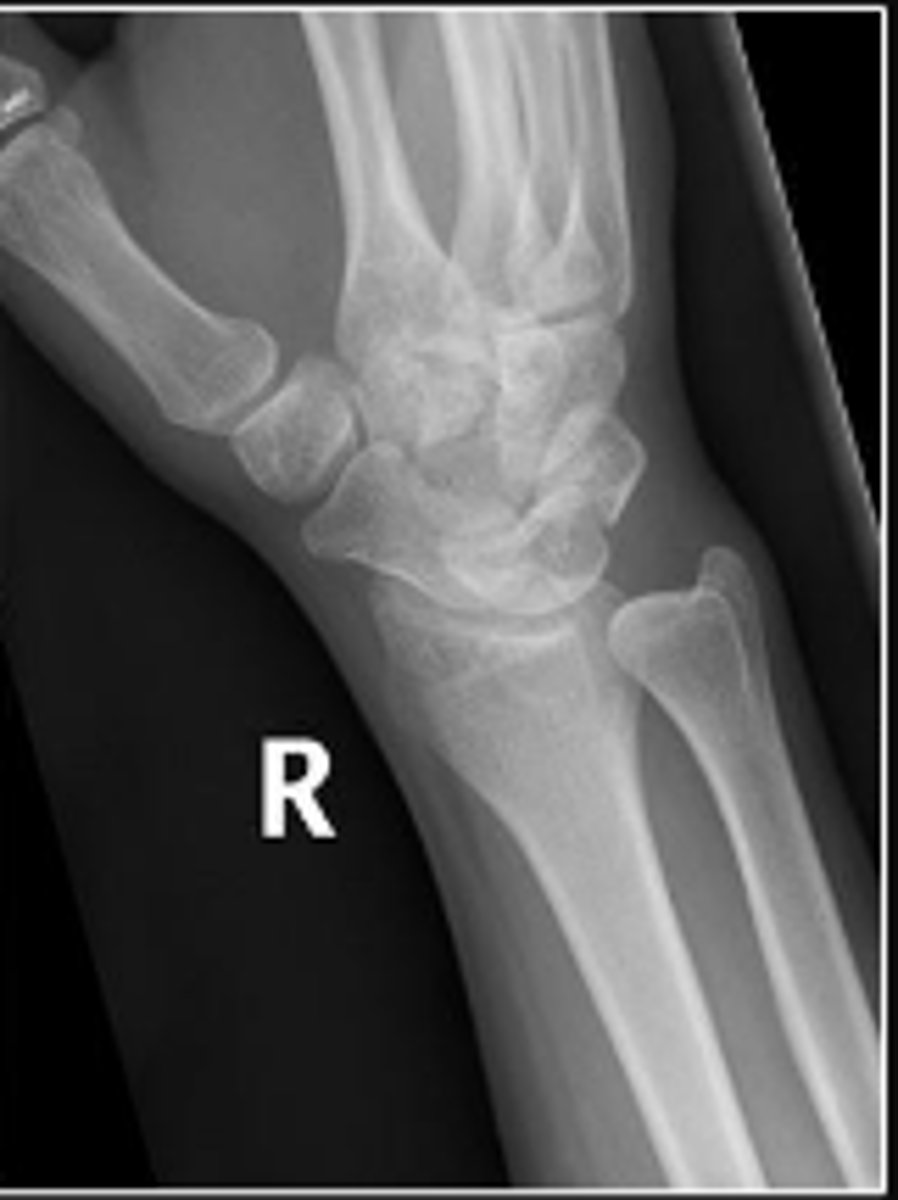

Medial oblique of the right wrist

What is the name of the radiographic view?